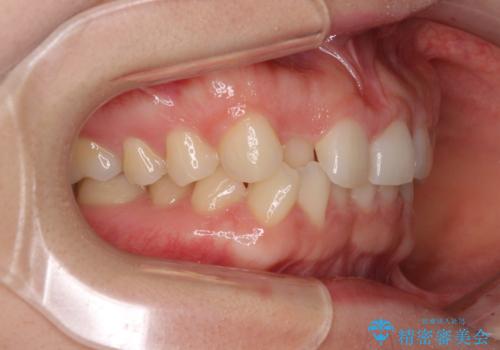

- 前歯の隙間やクロスバイトを気にして来院された患者様です。

結婚式の予定があり、可能であれば結婚式までに治療を終えたいとのことで、短期間で治療をおける可能性の高いワイヤー装置にて矯正治療を行うこととしました。